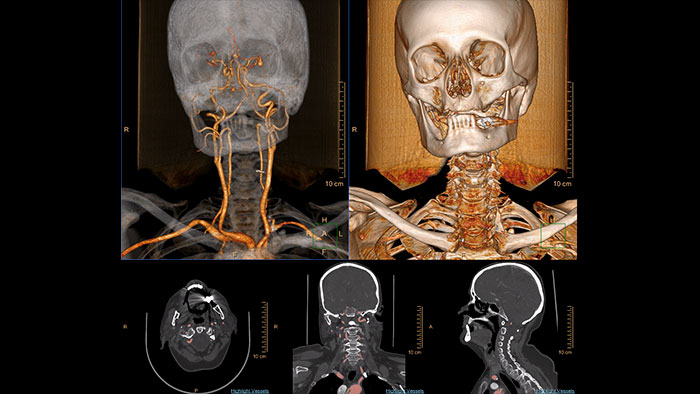

Advanced Vessel Analysis (AVA)

Multi Modality Advanced Vessel Analysis (AVA)

Comprehensive vascular analysis planning

Designed to examine and quantify different types of vascular lesions from CTA and MRA scans. It accommodates different modes of inspection, allows labeling different vascular lesions, and helps navigating through multiple findings.

Demonstrated to reduce the post-processing time by 50% when compared to manual Head & Neck CT angiography (CTA) analysis*.

advanced vessel analysis thumbnail

Benefits

• Ability to choose which Head & Neck Bone Removal method to be used (Standard vs. Smooth).

• Customizable Volume rendering “smoothness” for the 3D Head & Neck vascular structure using a smoothness control.

* Ardley N et al. Efficacy of a new post processing workflow for CTA head and neck. ECR 2013 / C-1760.